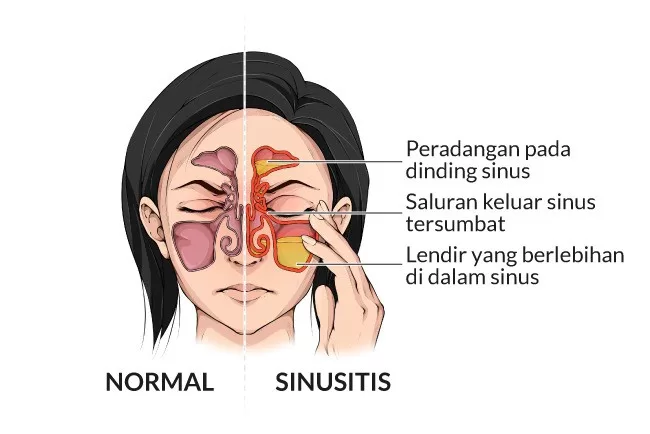

9. Sinusitis

Sinusitis adalah kelainan karena radang pada sinus. Sinus letaknya di daerah pipi kanan dan kiri batang hidung.. Biasanya di dalam sinus terkumpul nanah yang harus dibuang melalui operasi.